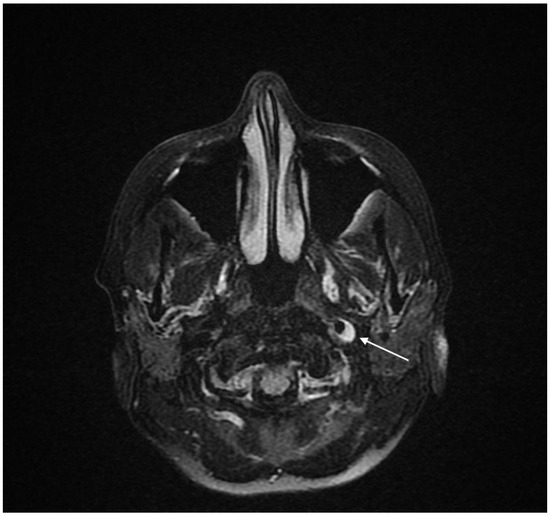

2.2. Diagnosis